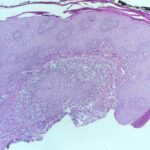

Histopathology. Early lesions no more than 2 or 3 months old show a nonspecific inflammatory infiltrate composed of neutrophils, monocytes, and macrophages. In lesions about 4 months old, a few multinucleated giant cells and a few small epithelioid cell granulomas usually are present, and in lesions 6 months old or older, typical tubercles or tuberculoid structures may be seen (126). Areas of necrosis are only occasionally present in the centers of the granulomas. The epidermis often shows marked hyperkeratosis with an acute inflammatory infiltrate and ulceration . |

Acid-fast bacilli usually can be identified in histologic sections of early lesions that show a nonspecific inflammatory infiltrate. In contrast, tuberculoid granulomas generally no longer show acid-fast organisms unless areas of central necrosis are present. Although primary lesions usually require a few months for the formation of tuberculoid granulomas, the sporotrichoid nodules that arise later show tuberculoid granulomas and a lack of acidfast bacilli even when they have been present for only a few weeks. |

Differential Diagnosis. The granulomatous reaction produced by M. marinum is similar to that observed in tuberculosis verrucosa cutis or lupus vulgaris. The pattem of pseudoepitheliomatous hyperplasia with granulomas and polymorphonuclear neutrophil infiltrate is also seen in several cutaneous mycoses (e.g., sporotrichosis and chromoblastomycosis), so fungal stains need to be examined alongside Ziehl-Neelsen stains. For definitive identification, culture may be necessary. |

Histopathology. The infection begins as a subcutaneous nodule exhibiting "ghost" ischemic-type dermal collagen and fat necrosis with deposition of fibrin and hematoxyphilic extracellular clumps of mycobacteria. Ulceration proceeds as the epidermis loses its vascular supply. Ziehl-Neelsen stains reveal vast numbers of acid-fast bacilli in the necrotic fat ; their distribution is often irregular. A variable degree of neutrophil infiltration and thrombosis of vessels are also observed. In time, a nonspecific granulation tissue or a granulomatous reaction commences from the depth and sides of the ulcer; healing and re-epithelialization take place with considerable scarring. Acid-fast bacilli decline rapidly in number during healing . The histopathologic case definition for Buruli ulcer, useful for research studies, is (a) the typical pattern of infarctivelike necrosis of deep dermal collagen and fat and (ideally, but not always found in limited samples) (b) nearby clusters of acid-fast bacilli. |